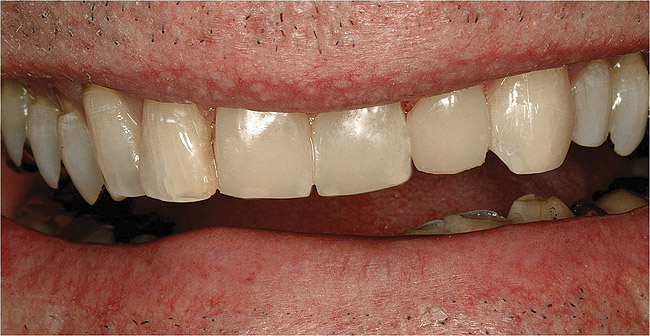

Figure  3  Severe dental erosion and attrition in a GERD patient.

Figure 3

Characteristics of damage to tooth structures caused by acidity include wear on the occlusal surfaces of molars and a saucer shape on the cusps of molars (perimolysis).12 The erosion can vary from minor and subtle changes on the tooth surface, ie, loss of luster, a dull or matted look, to cupping on occlusal surfaces or incisal edges, which may extend to dentin. Usually, the erosive lesions demonstrate greater width than depth. When combined with abrasive forces or stresses, the tooth surface loss may occur at a faster rate (Figure 2, Figure 3, Figure 4 and Figure 5).